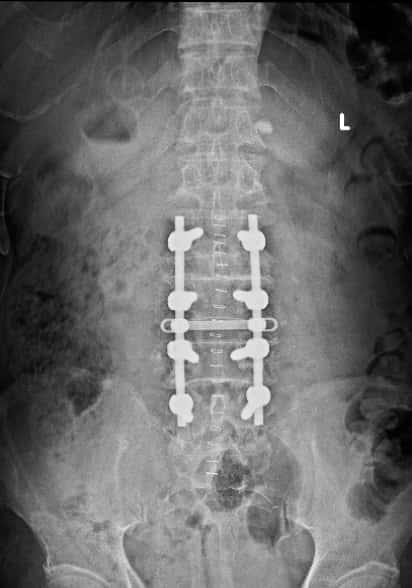

腰椎术后正位片

手术顺利,麻醉师功不可没!整个减压内固定的时间1小时23分钟,手术中出血约200毫升,出血回吸收122毫升。手术后右下肢疼痛消失,术后第四天下地行走,双下肢活动正常。术后两周一切平稳,没有出现高血压,心脏病相关的并发症。